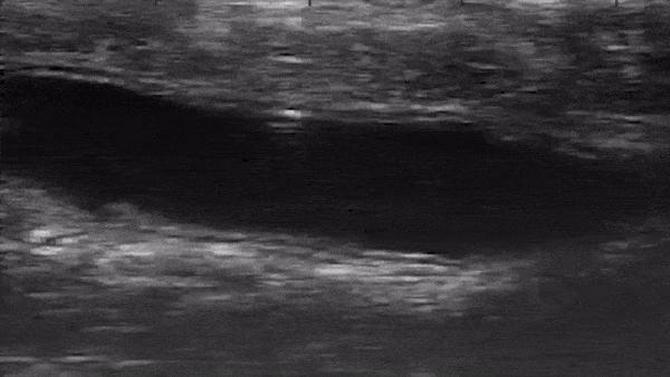

Imagen de ultrasonido que muestra a un microrrobot dando vueltas por un colon in vivo. (Foto: Purdue University/Elizabeth Niedert y Chenghao Bi)

El equipo llevó a cabo los experimentos in vivo en el colon de ratones vivos bajo anestesia, insertando el microrrobot en una solución salina a través del recto. Utilizaron un equipo de ultrasonidos para observar en tiempo real lo bien que se movía el microrrobot.